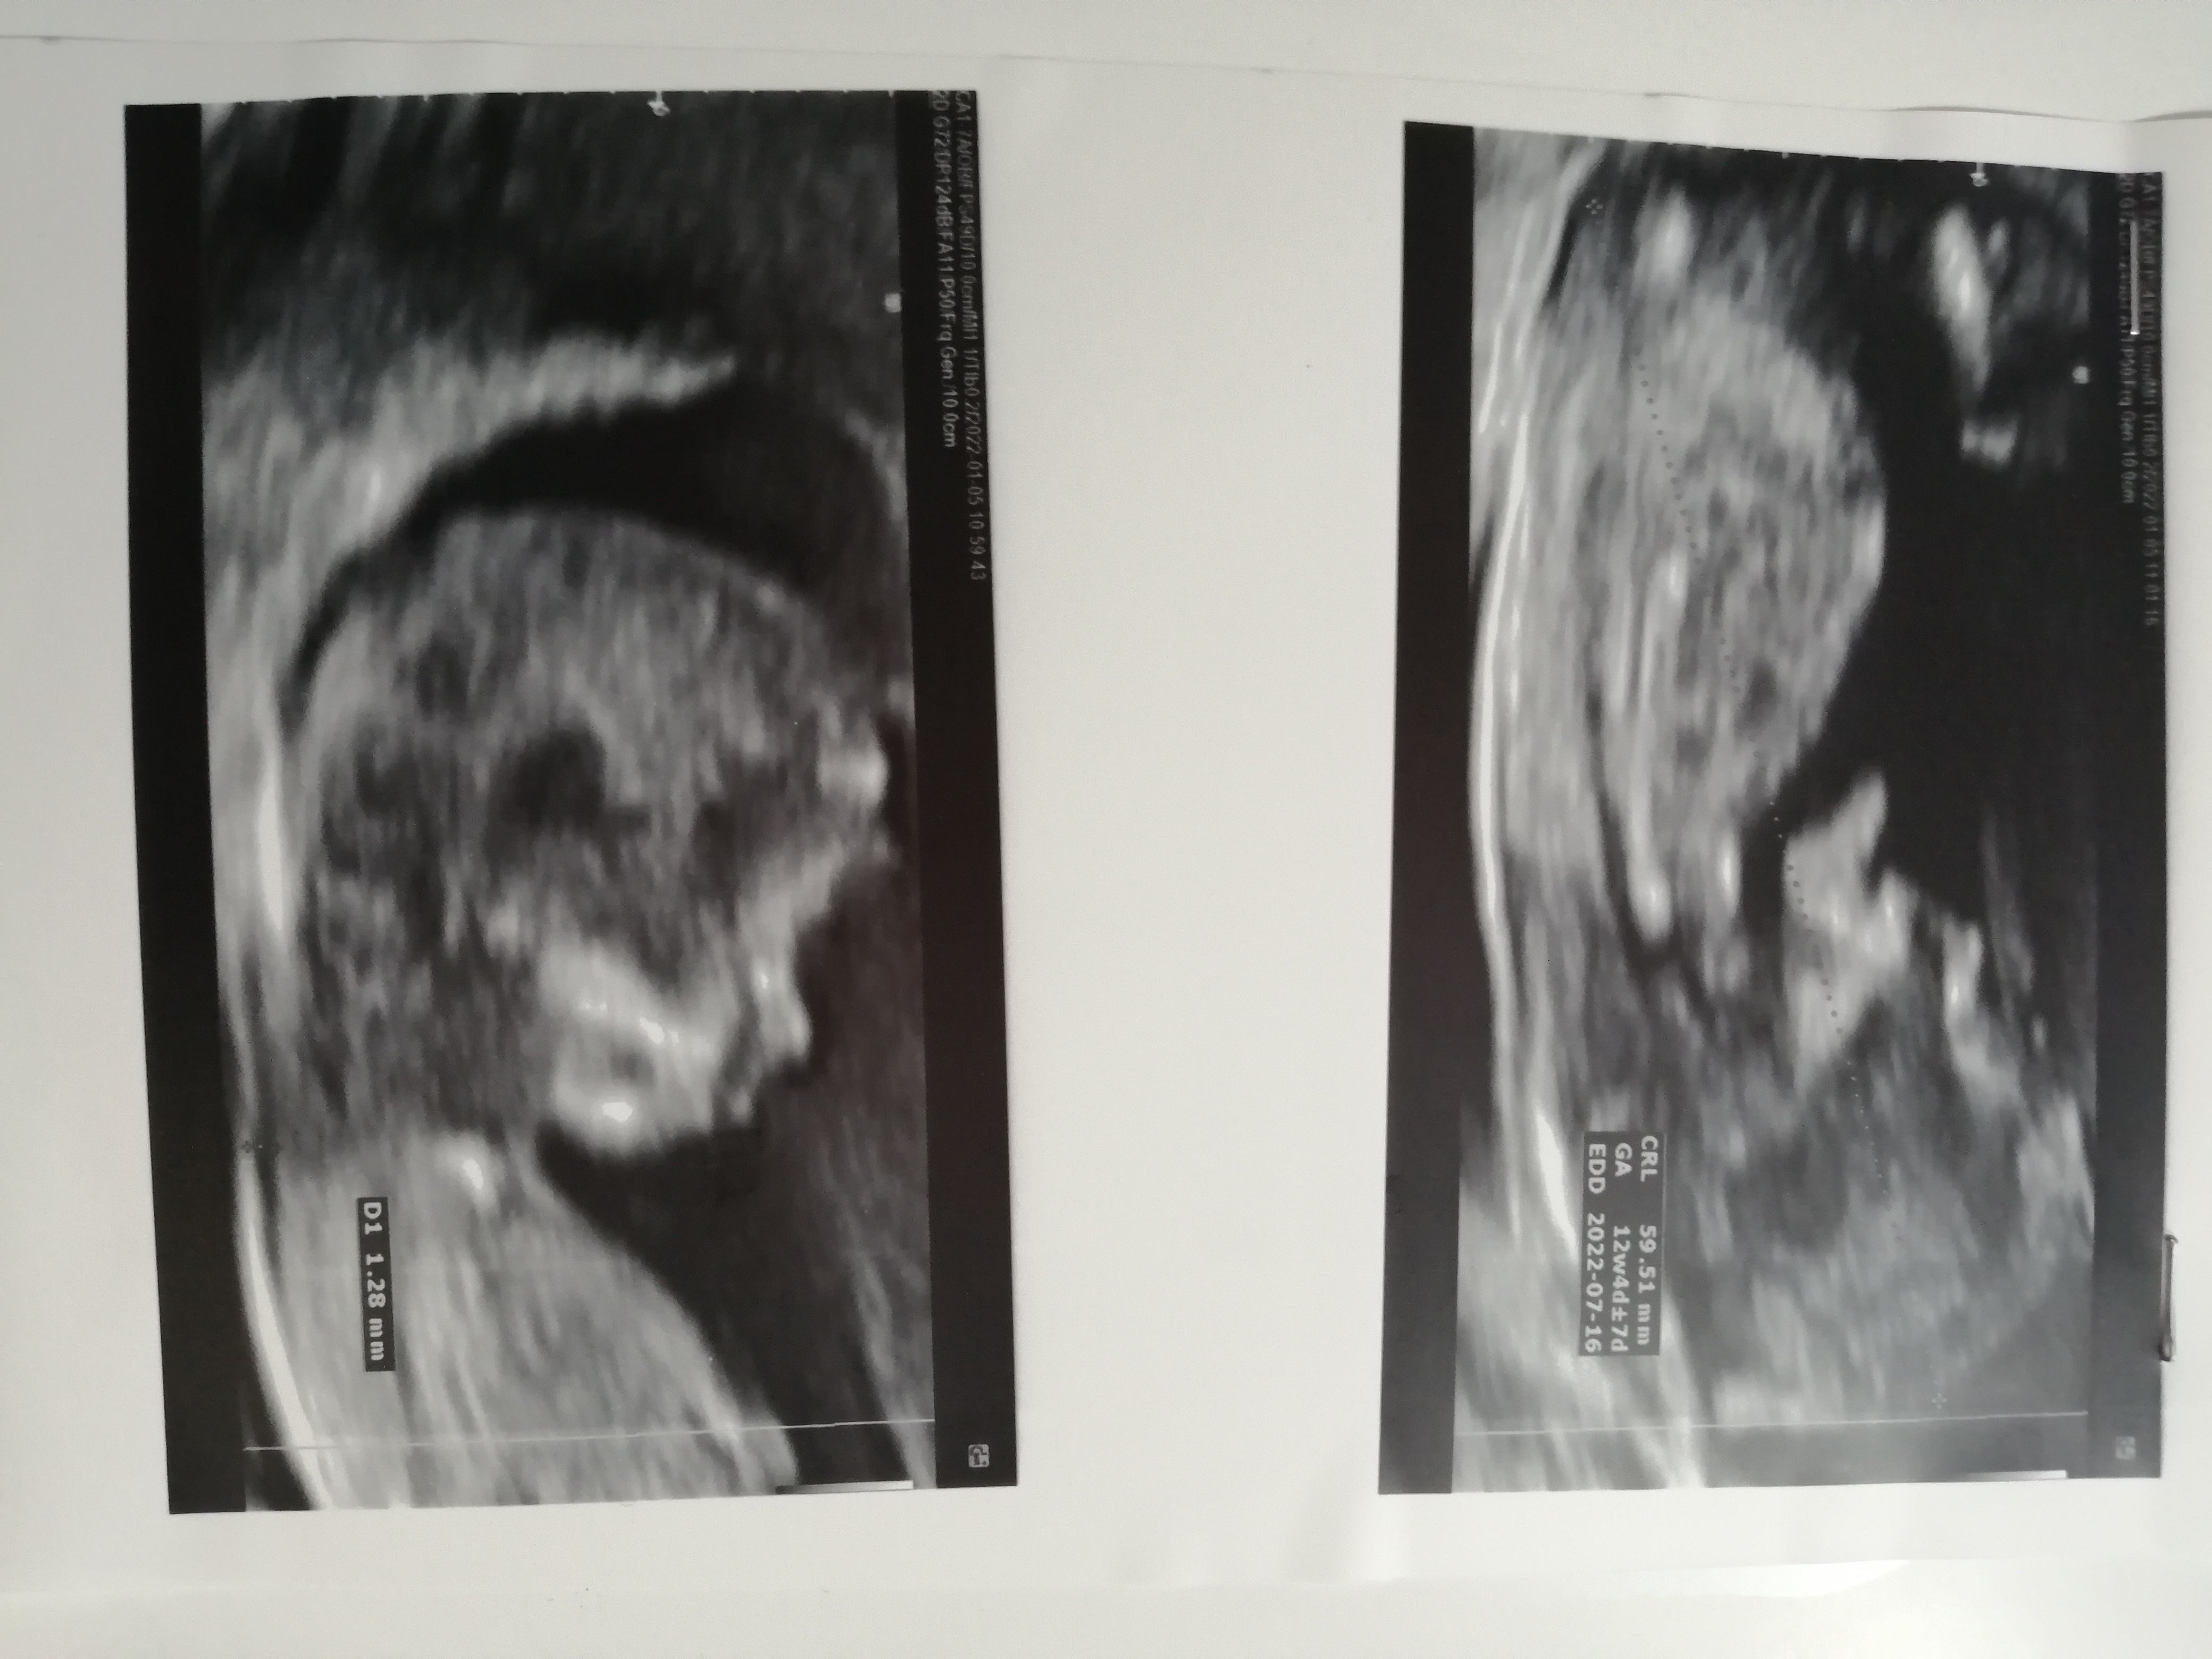

بیبیتذ مدیر استارتر عضویت: 1398/12/09 تعداد پست: 811 عنوان تعیین جنسیت 132 بازدید | 5 پست بچم دختره یا پسر؟ 1402/01/10 | 12:20 0 نفر لایک کرده اند ... گزارش تاپیک نامناسب